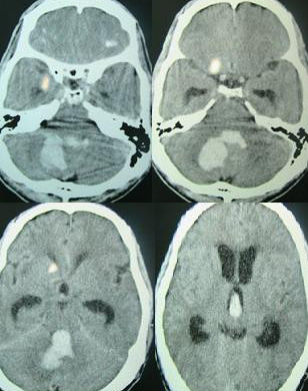

脑溢血也就是人们口中常说的脑出血,在神经科是常见的现象,是指非外伤性脑内血管破裂引起的出血。我们人体的大脑由头骨仅仅包围着,任何从出血中渗出的血液都会对脑组织造成压迫和损伤。如果大脑中的血管泄漏或破裂并引起出血,就会发生出血性中风。近几年来,脑溢血逐渐成为广泛发生的急性病,多发病于40岁以上的中老年人。目前我国每年因为脑溢血而死亡的患者已达全部疾病死亡人数的20%,因为其发病快、病情凶险,不能得到及时的治疗,成为病死率较高的疾病之一。

2、颅内动脉瘤、脑血管畸形和颅内恶性肿瘤:颅内动脉瘤和脑血管畸形是蛛网膜下腔出血的常见原因,蛛网膜下腔出血还会导致几大并发症,比如缺血性脑卒中的发作,有可能会引发患者偏瘫,失语,卧床,甚至出现痴呆等。而颅内恶性肿瘤,比如胶质瘤、转移瘤、黑色素瘤等,发生肿瘤卒中时可形成脑内出血。多次出血可能导致患者死亡,而且其肿瘤本身就是具威胁性的。